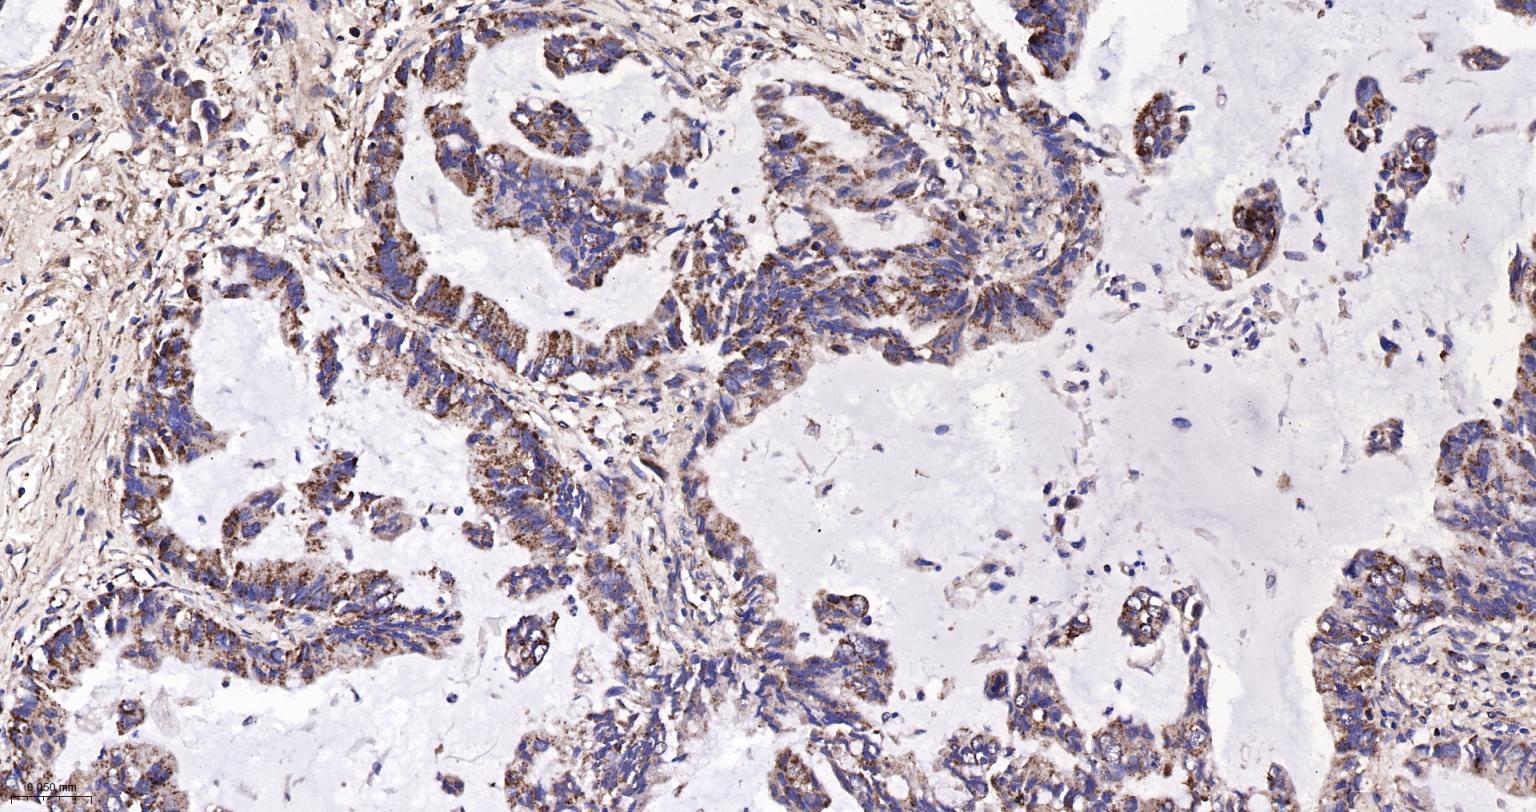

Paraformaldehyde-fixed, paraffin embedded Human Lung Cancer; Antigen retrieval by boiling in sodium citrate buffer (pH6.0) for 15 min; The section was incubated with IDH2 Monoclonal Antibody, Unconjugated (bsm-61585R) at 1:200 overnight at 4°C, followed by conjugation to the bs-0295G-HRP and DAB (C-0010) staining.